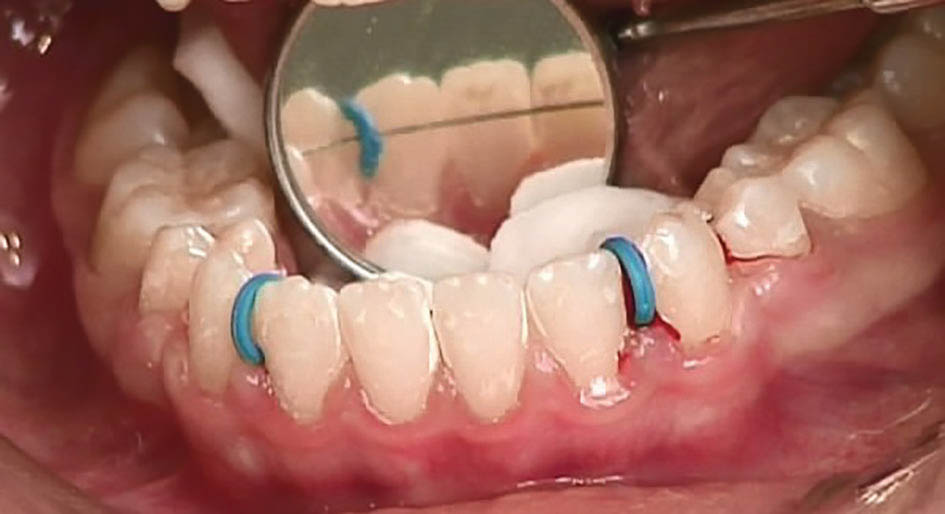

سیم را روی سینگلوم قرار دهید. اگر درون حفره دهان نیاُفتاد که مشغول چسباندن آن میشوید. اگر روی سینگلوم قرار نمیگیرد باید دو عدد سپراتور پلاستیکی بین دندانهای 2و3 دو طرف قرار دهید و سیم را از زیر آن رد کنید تا محکم به سینگلوم بچسبد (شکل 71-4). میتوانید دو سه قطعه نخ دندان بردارید و هرکدام را از کنتاکت بین دندانها رد کنید و سیم را بگذارید روی آن و بعد نخها را گره بزنید تا سیم در محل خود محکم شود.

ابتدا سطح سینگلوم دندانها را با پودر اکسید آلومینیوم 50 میکرون سندبلاست کنید و سپس با اسید اچ و رزین سطح سینگلوم را آماده میکنید. رزین را اشعه بدهید تا کیور شود و بعد با کامپوزیت ارتودنسی سیم را به دندان متصل نمایید. خیلی مراقب باشید تا سطح دندان با بزاق آلوده نشود. بعد از کیور شدن برای خارج کردن سپراتور میتوانید آن را با نوک سوند از روی دندان بلند کنید و با قیچی یا کاتر آن را قطع کنید (شکل 72-4) و سپراتور را از لای امبراژور دندان خارج کنید.

شکل 71-4: قراردادن سیم Twisted به کمک سپراتور